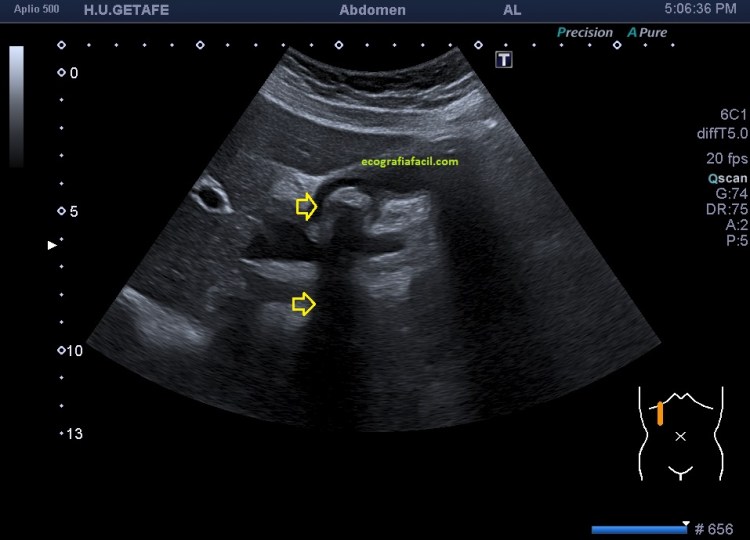

En esta primera imagen observas la normalidad de la vesícula biliar, donde puedes ver una ecoarquitectura sacular, anecoica, de paredes finas, con una excelente capacidad de transmitir el sonido. Las ayunas hacen que la vesícula se vea repleccionada.